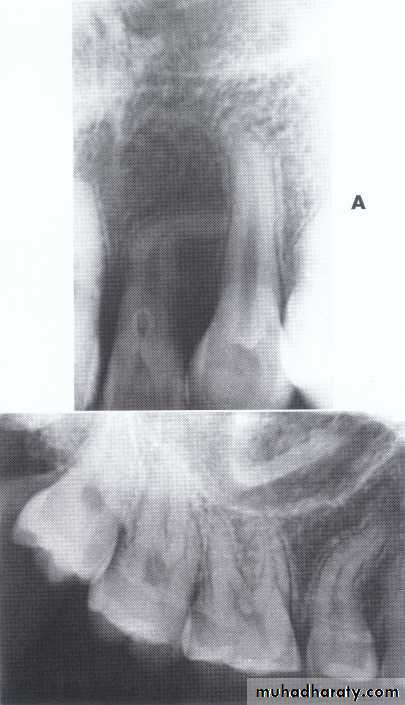

Dentin dysplasia, type I. panoramic & periapical films of the same case show the short and poorly developed roots, obliterated pulp chambers and root canals, and periapical inflammatory lesions.

Dentin dysplasia, type II. panoramic &periapical films of the same case show obliteration of the pulp chamber, reduction in the caliber of root canals, and pulp stones obscuring the flame-shaped pulp chambers.

Periapical inflammatory lesions are associated with some of the mandibular anterior teeth.